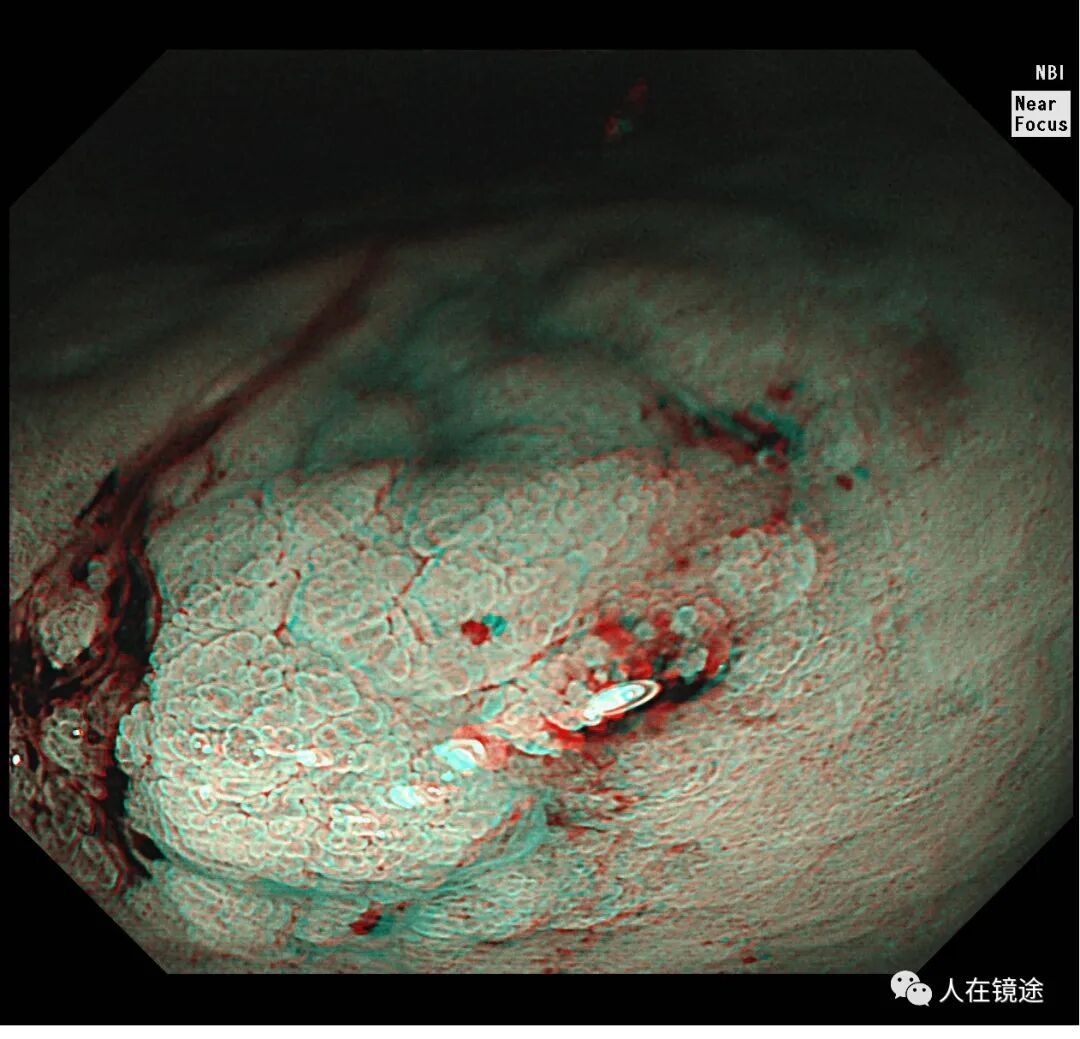

NBI+近焦示:胃窦小弯见一0.8*1.2cmIIa粘膜发病变呈咖色,边界清楚,微结构紊乱,表面粘膜高低不平伴自发性出血